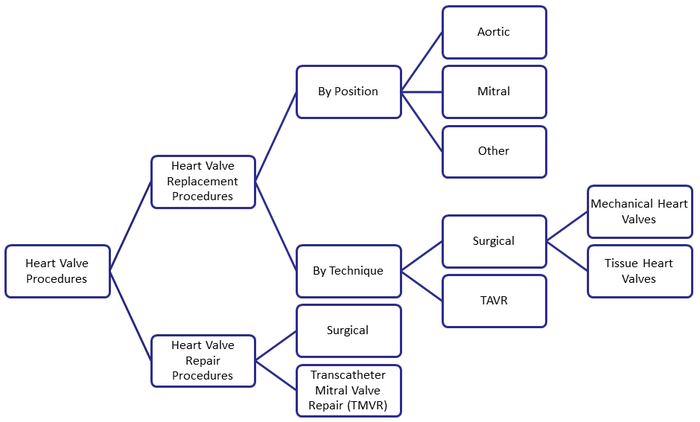

Heart valve procedures

Procedure of Heart Valve Surgery

Heart valve surgery means repair or replacement of the diseased valves. In the surgery, some valves are repaired or mended to do its work properly. Replacement means removal of the diseased valves by a new valve. The procedures of heart valve surgery are :

- Valve Repairing : In the valve repair surgery, a ring is sewn around the opening of the valve to make tighter. The surgeons may cut the other parts or may separate and shorten it to help the valve open and close right.

- Valve Replacement : Sometimes by mending the valves, it is not possible to cure the unhealthy valve, and then replacement is required to get back its normal function. A prosthetic valve is used to replace. There are two types of prosthetic valves.

- Mechanical valves : These types of valves are made from man-made materials. While heart surgeons’ use this valve, lifetime therapy with an anticoagulant is prescribed to the patient.

- Biological (tissue) valves : The surgeons take biological valves from pig, cow or human donors. The longevity of biological valves is less than the mechanical valves.

Heart valve procedures by technique